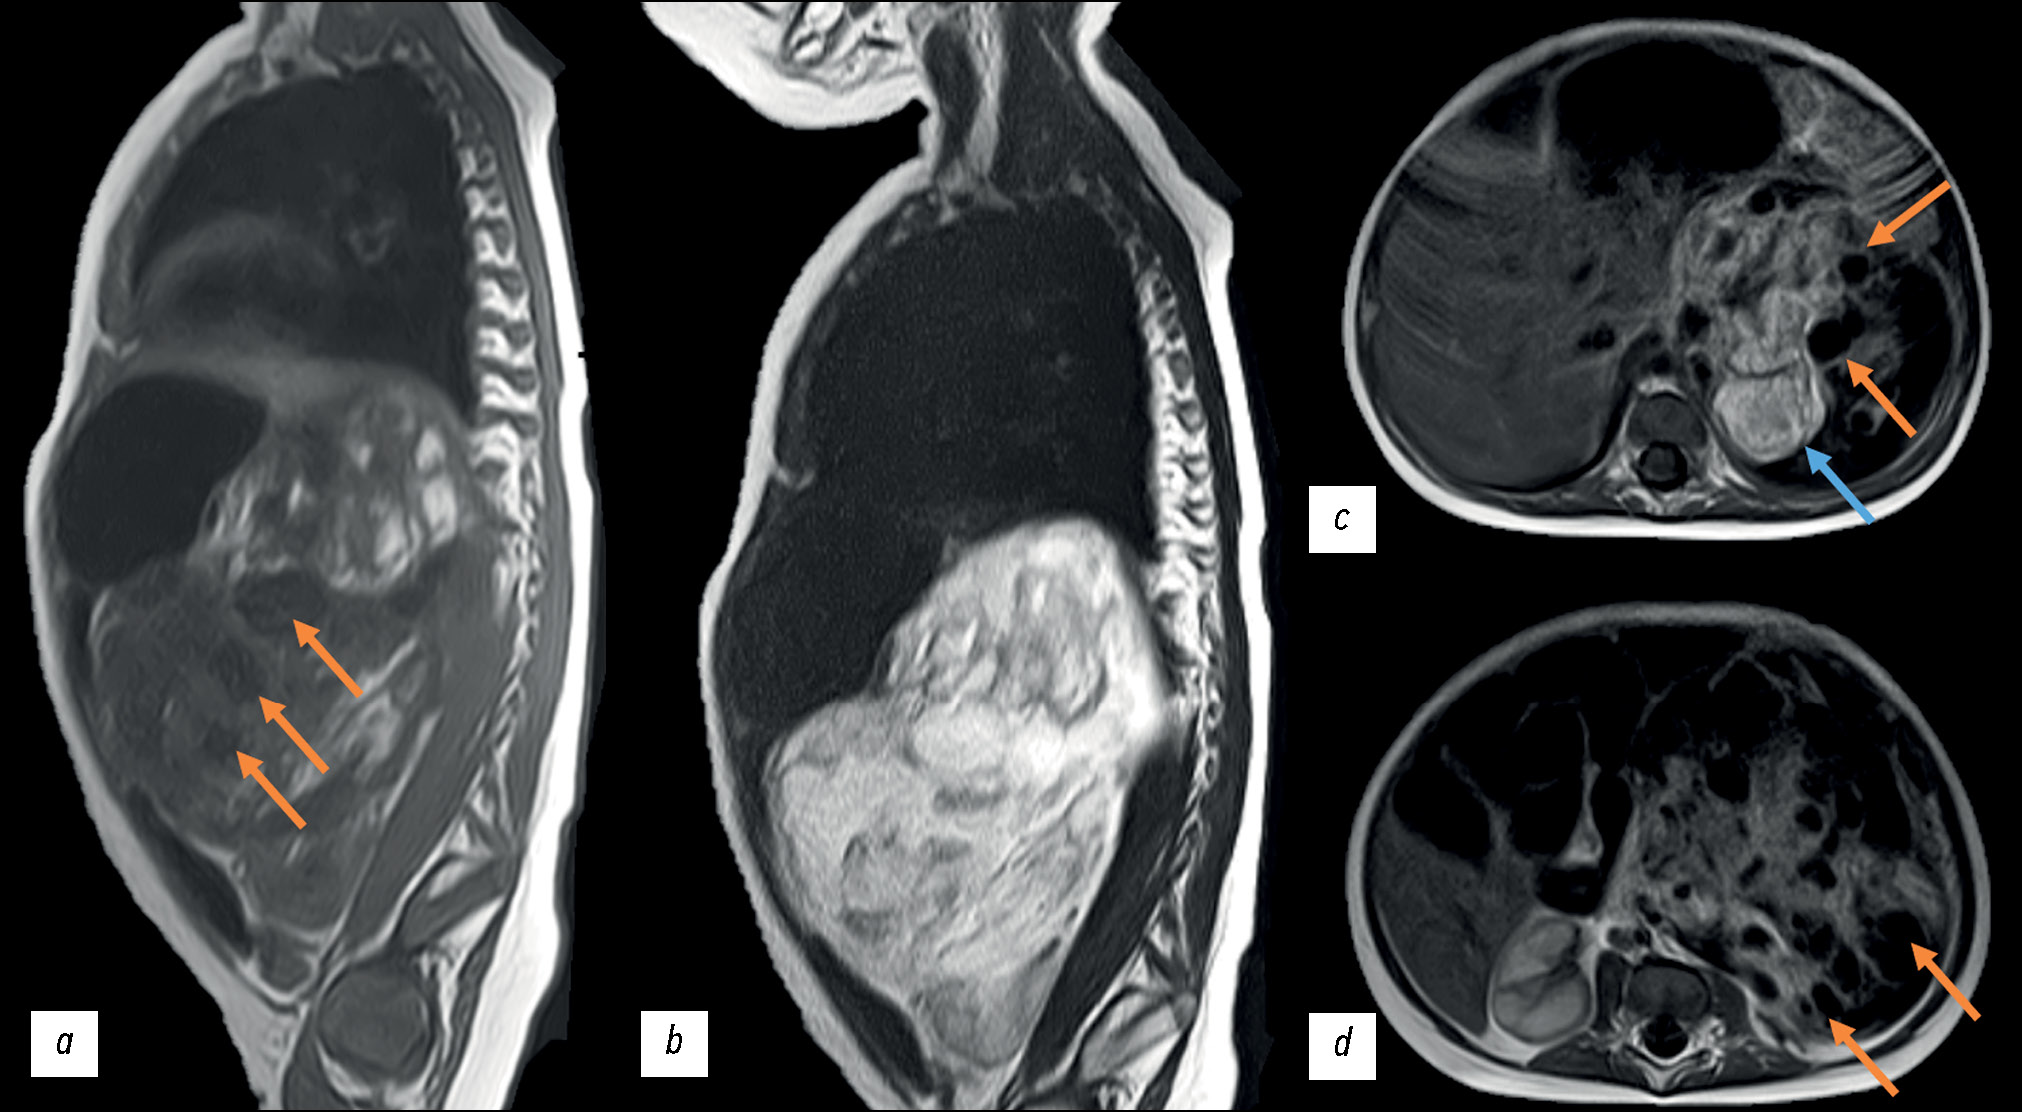

October 16, 2020: The patient was referred for follow-up magnetic resonance imaging (MRI) at their place of residence. The MRI revealed disease progression, with a tumor size increase to 104 × 77 × 118 mm (volume: 491 cm3). The tumor exhibited a cystic and solid structure, with areas of hemorrhage and signs of active contrast uptake. The adrenal gland was spread along the lateral contour of the tumor. The tumor contour was followed by the renal vessels on the left; the superior mesenteric artery was displaced to the right, and the celiac artery was displaced upward. The study did not incorporate contrast sequences or weighted sequences with fat suppression (Fig. 2).

Fig. 2. Abdominal magnetic resonance imaging dated November 16, 2020: (a) Т1-weighted image, sagittal plane; (b) Т2-weighted image, sagittal plane; (c, d) Т1-weighted images, axial plane; a space-occupying mass of the left adrenal gland, with an increase in the size over time. Orange arrows indicate an attenuated signal from the cystic tumor component; the blue arrow indicates an enhanced signal from the solid tumor component.